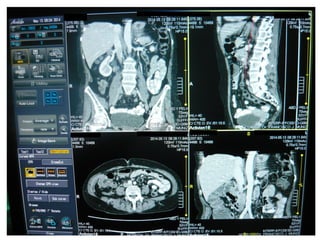

MPRMPR Reconstrucción Multiplanar

Es una deformación geométrica del volumen

de datos. No es 3D.

Suele ser la más utilizada. Permite visualizar el

volumen.

Las reconstrucciones multiplanares deben ser

calculadas a partir de voxels isotrópicos (voxels

con lados iguales en las tres dimensiones del

espacio)